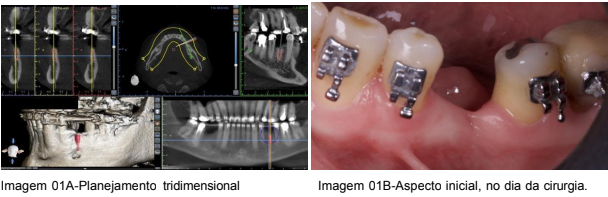

Após uma anamnese detalhada, o paciente foi submetido a exames clínicos e de imagem (tomografia computadorizada), que confirmaram a necessidade de um aumento ósseo horizontal para criar a base óssea necessária para a instalação dos implantes. A tomografia revelou a redução da largura óssea na região posterior da mandíbula, em torno do local onde o implante seria instalado.

A decisão foi tomada em conjunto com o paciente para realizar o aumento ósseo utilizando a técnica de Khoury. Para o planejamento da cirurgia, foi realizada uma análise digital da situação clínica, e o planejamento tridimensional foi feito com o auxílio do CAD/CAM, permitindo a visualização precisa da área a ser enxertada e a criação de uma estratégia de incisão, remoção do enxerto ósseo e posicionamento do implante. (Imagem 01a e imagem 01b)

Fonte: próprio autor